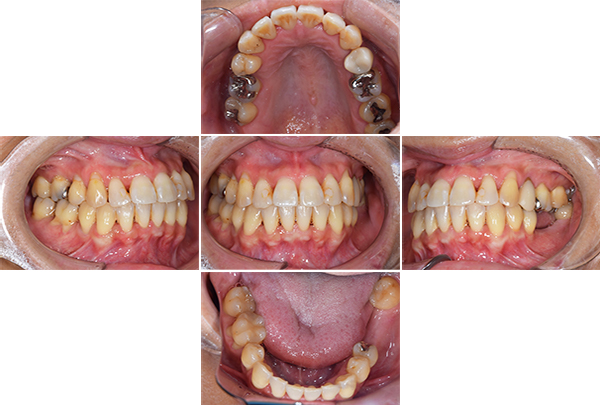

症例写真(治療前)

治療前:

八重歯が目立ちます。また銀歯もおおく、見た目が気になります。虫歯も散見できます。